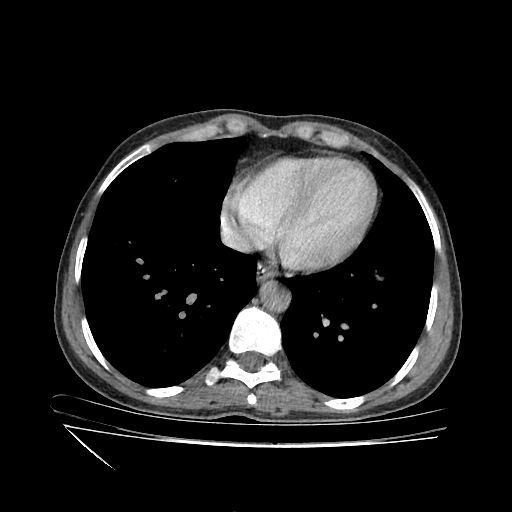

Original VENOUS CT scan

No window - Raw intensity values

Lung window (WL -600, WW 1500 β†’ Low βˆ’1350, High +150)

Mediastinum window (WL 40, WW 400 β†’ Low βˆ’160, High +240)